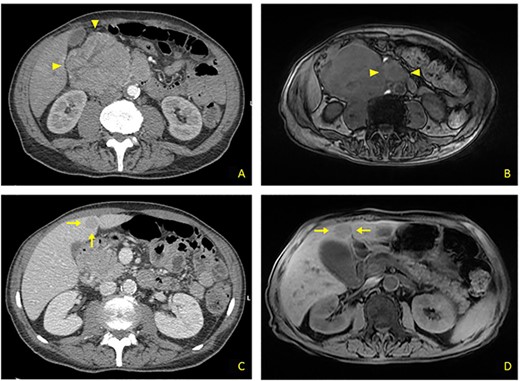

(A) Contrast CT scan: bulky formation with inhomogeneous uptake, arising from upper duodenal-pancreatic angle (arrowheads). (B) MRI: main lesion appears hypointense on fat-suppressed T1-weighted sequences. Evidence for further retromesenteric contrast enhanced tissue (arrowheads). (C) Contrast CT scan: hypodense rounded liver metastasis arising from segment V, measuring 2.5 cm in diameter (arrows). (D) MRI: T1-appearance of subglissonian pericholecystic liver metastasis (arrows).

A 68-year-old male was admitted to our Ward Unit reporting dyspepsia, weakness with weight loss and abdominal pain. Neither previous abdominal surgery nor a family history of cancer was referred. Patient complained of pain on the right flank (4.5 points in the Pain Scale Chart); canalization and food intake were described as regular. A large mass occupying the right abdomen was easily detected. Basic laboratory panel revealed anemia (Hb 9.8 g/dl) without leukocytosis or jaundice. Body mass index was 19.5 and KPS 70%. AngioCT revealed a neoplasm measuring 11 × 8.5 × 8 cm arising from the upper duodenal-pancreatic angle (Fig. 1A). Endoscopy confirmed its duodenal origin, but biopsies were not diagnostic. Prohance® MRI showed possible involvement of right colon and root of transverse mesocolon, with evidence of retromesenteric contrast enhanced tissue (Fig. 1B). Single liver metastasis, 2.5 cm in diameter, arising from segment V, was found (Fig 1C and D). Panel of tumoral markers showed increased values of chromogranin A and neuron-specific enolase, suggesting a diagnosis of nonfunctioning duodenal NET. Procedure-related morbidity contraindicated a percutaneous biopsy, hence diagnostic laparoscopy was performed: it confirmed the absence of peritoneal seeding and allowed a percutaneous 16G Tru-cut biopsy both for tumoral bulk and liver metastasis (Fig. 2A and B). Both samples showed a high-degree NET (G3). A 68Ga-DOTATOC PET/CT excluded any extra-abdominal disease, so the multidisciplinary board authorized a direct surgical approach.